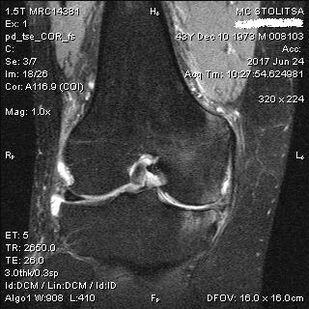

Diagnosis of arthrosis of the knee joint is carried out in the office of a rheumatologist or orthopedist.The doctor examines the affected joint, feels it, listens to complaints and asks additional questions.Carrying out some tests - for example asking the patient to bend their legs or take a few steps.Then, if it is necessary to clarify the stage of the disease or the nature of pathological changes, he will refer you for additional research.For example, for computer tomography or radiography.